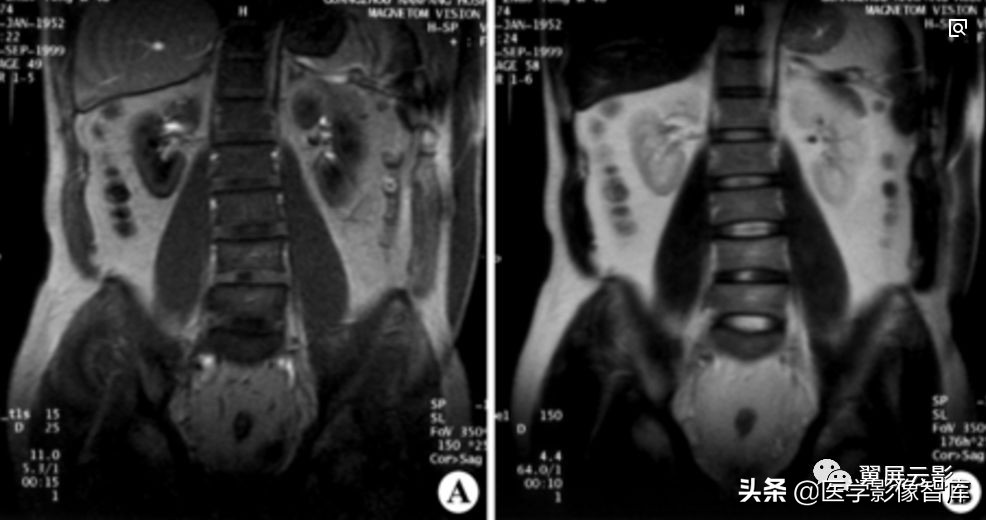

肾管交界部狭窄

左输尿管上端先天性狭窄并肾盂高度扩张积水

本病是常见的先天性异常,在新生儿及婴儿期是肾盂积水最常见的病因,梗阻的实际原因通常是狭窄,也可为迷走血管,纤维束带等外压所致。盂管交界部梗阻皆表现为肾盂积水,新生儿期的肋腹部肿块一半为肾盂积水所导致,有时在出生前即经超声诊断。

MRI及MRU表现为双侧或单侧肾盂肾盏不同程度的积水扩张,肾盂扩张往往更重且向前移位,盂管交界部变钝或呈鸟喙状,当积水严重时肾实质变薄,合并感染时皮髓质分界不清,增强检查强化程度减低,应该注意的是,由于输尿管内尿液很少,所以MRU常不显影,肾盂肾盏内继发结石常为多发沙砾状。继发感染性脓肾时肾破裂的情况也应予以重视。